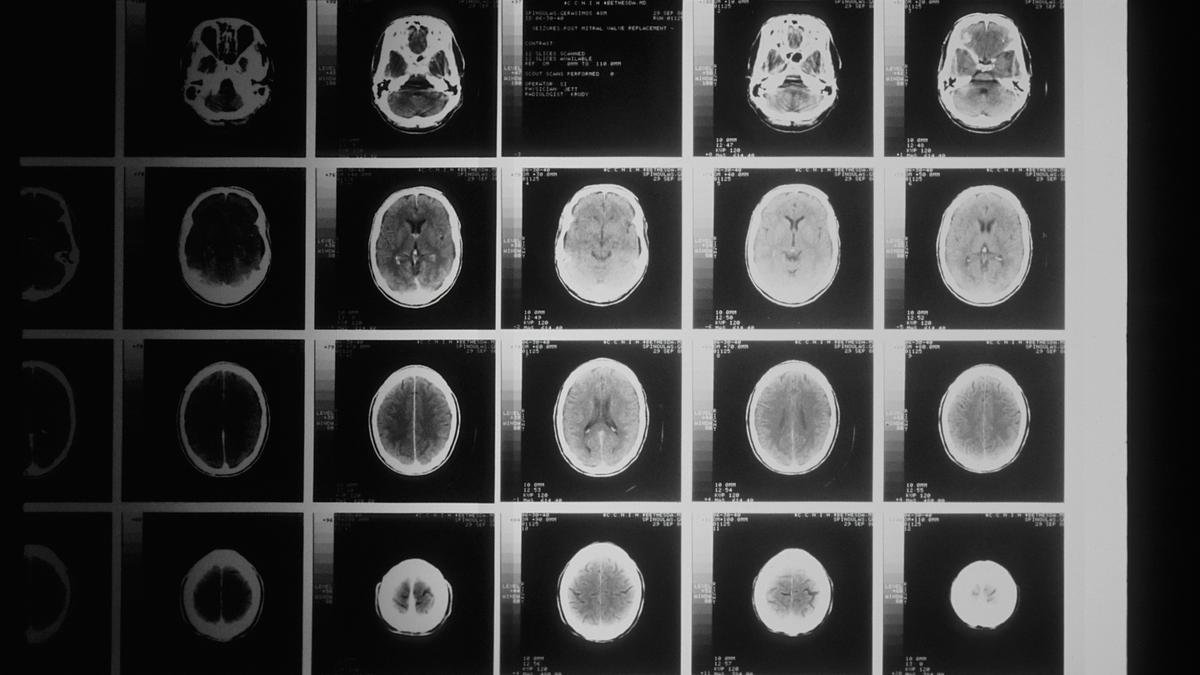

In the experiment, published in The Journal of Neuroscience on January 14, volunteers received DMT while researchers recorded their brain activity using electroencephalography (EEG) to track rhythmic electrical patterns across the scalp.

In normal conditions, one of the brain’s dominant rhythms is the alpha wave — a slow oscillation linked to inward focus. This rhythm helps regulate internally focused processing. Importantly, this rhythm is not the self itself but one neural signature associated with how the brain maintains a coherent sense of self over time.

During the DMT experience, that pattern began to loosen. Alpha rhythms weakened and lost coordination. Overall brain activity also shifted away from its usual organisation. And the more this rhythm weakened, the more strongly participants reported losing their ordinary sense of self.

A one-second sample from an EEG filtered to show the alpha waves.

| Photo Credit:

Hugo Gamboa (CC BY-SA)